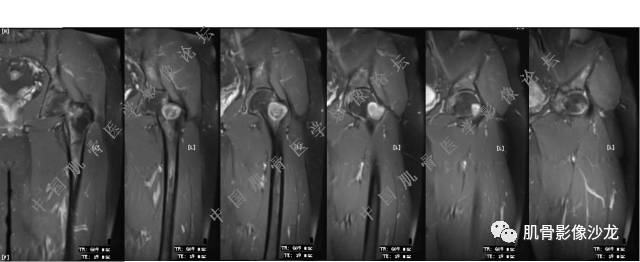

主诉:左髋疼痛1月余

现病史:患者1月余前无明显诱因出现左髋部疼痛,无明显活动受限,当地医院行X线检查,提示左股骨颈异常密度。遂来我院就诊。

既往史:曾患乙型肝炎,未正规治疗,目前无症状。

葛英霖 20:5 4 常规纤维类的多一些,冠状位没有看到明显脂肪。纤维结构不良、纤维组织细胞瘤、软粘纤之类。

夏威夷的风 20:55 大方向纤维类病变

Echo 20:55 考虑纤维类的依据是?

夏威夷的风 20:58 强化渐进性强化吧 边界清晰 里面也见线状低信号

飞鹰行动 21:01 良性纤维组织细胞瘤内部可以有少量脂肪

X(CT、MR)战警 21:01 泡沫细胞被吞噬后形成脂肪信号, bfh可以有脂肪条带样改变

Echo 21:04 总之这例就是各位老师说的硬化边明显,没有软组织肿块,没有侵犯,考虑良性病变,增强渐进性强化,所以考虑BFH